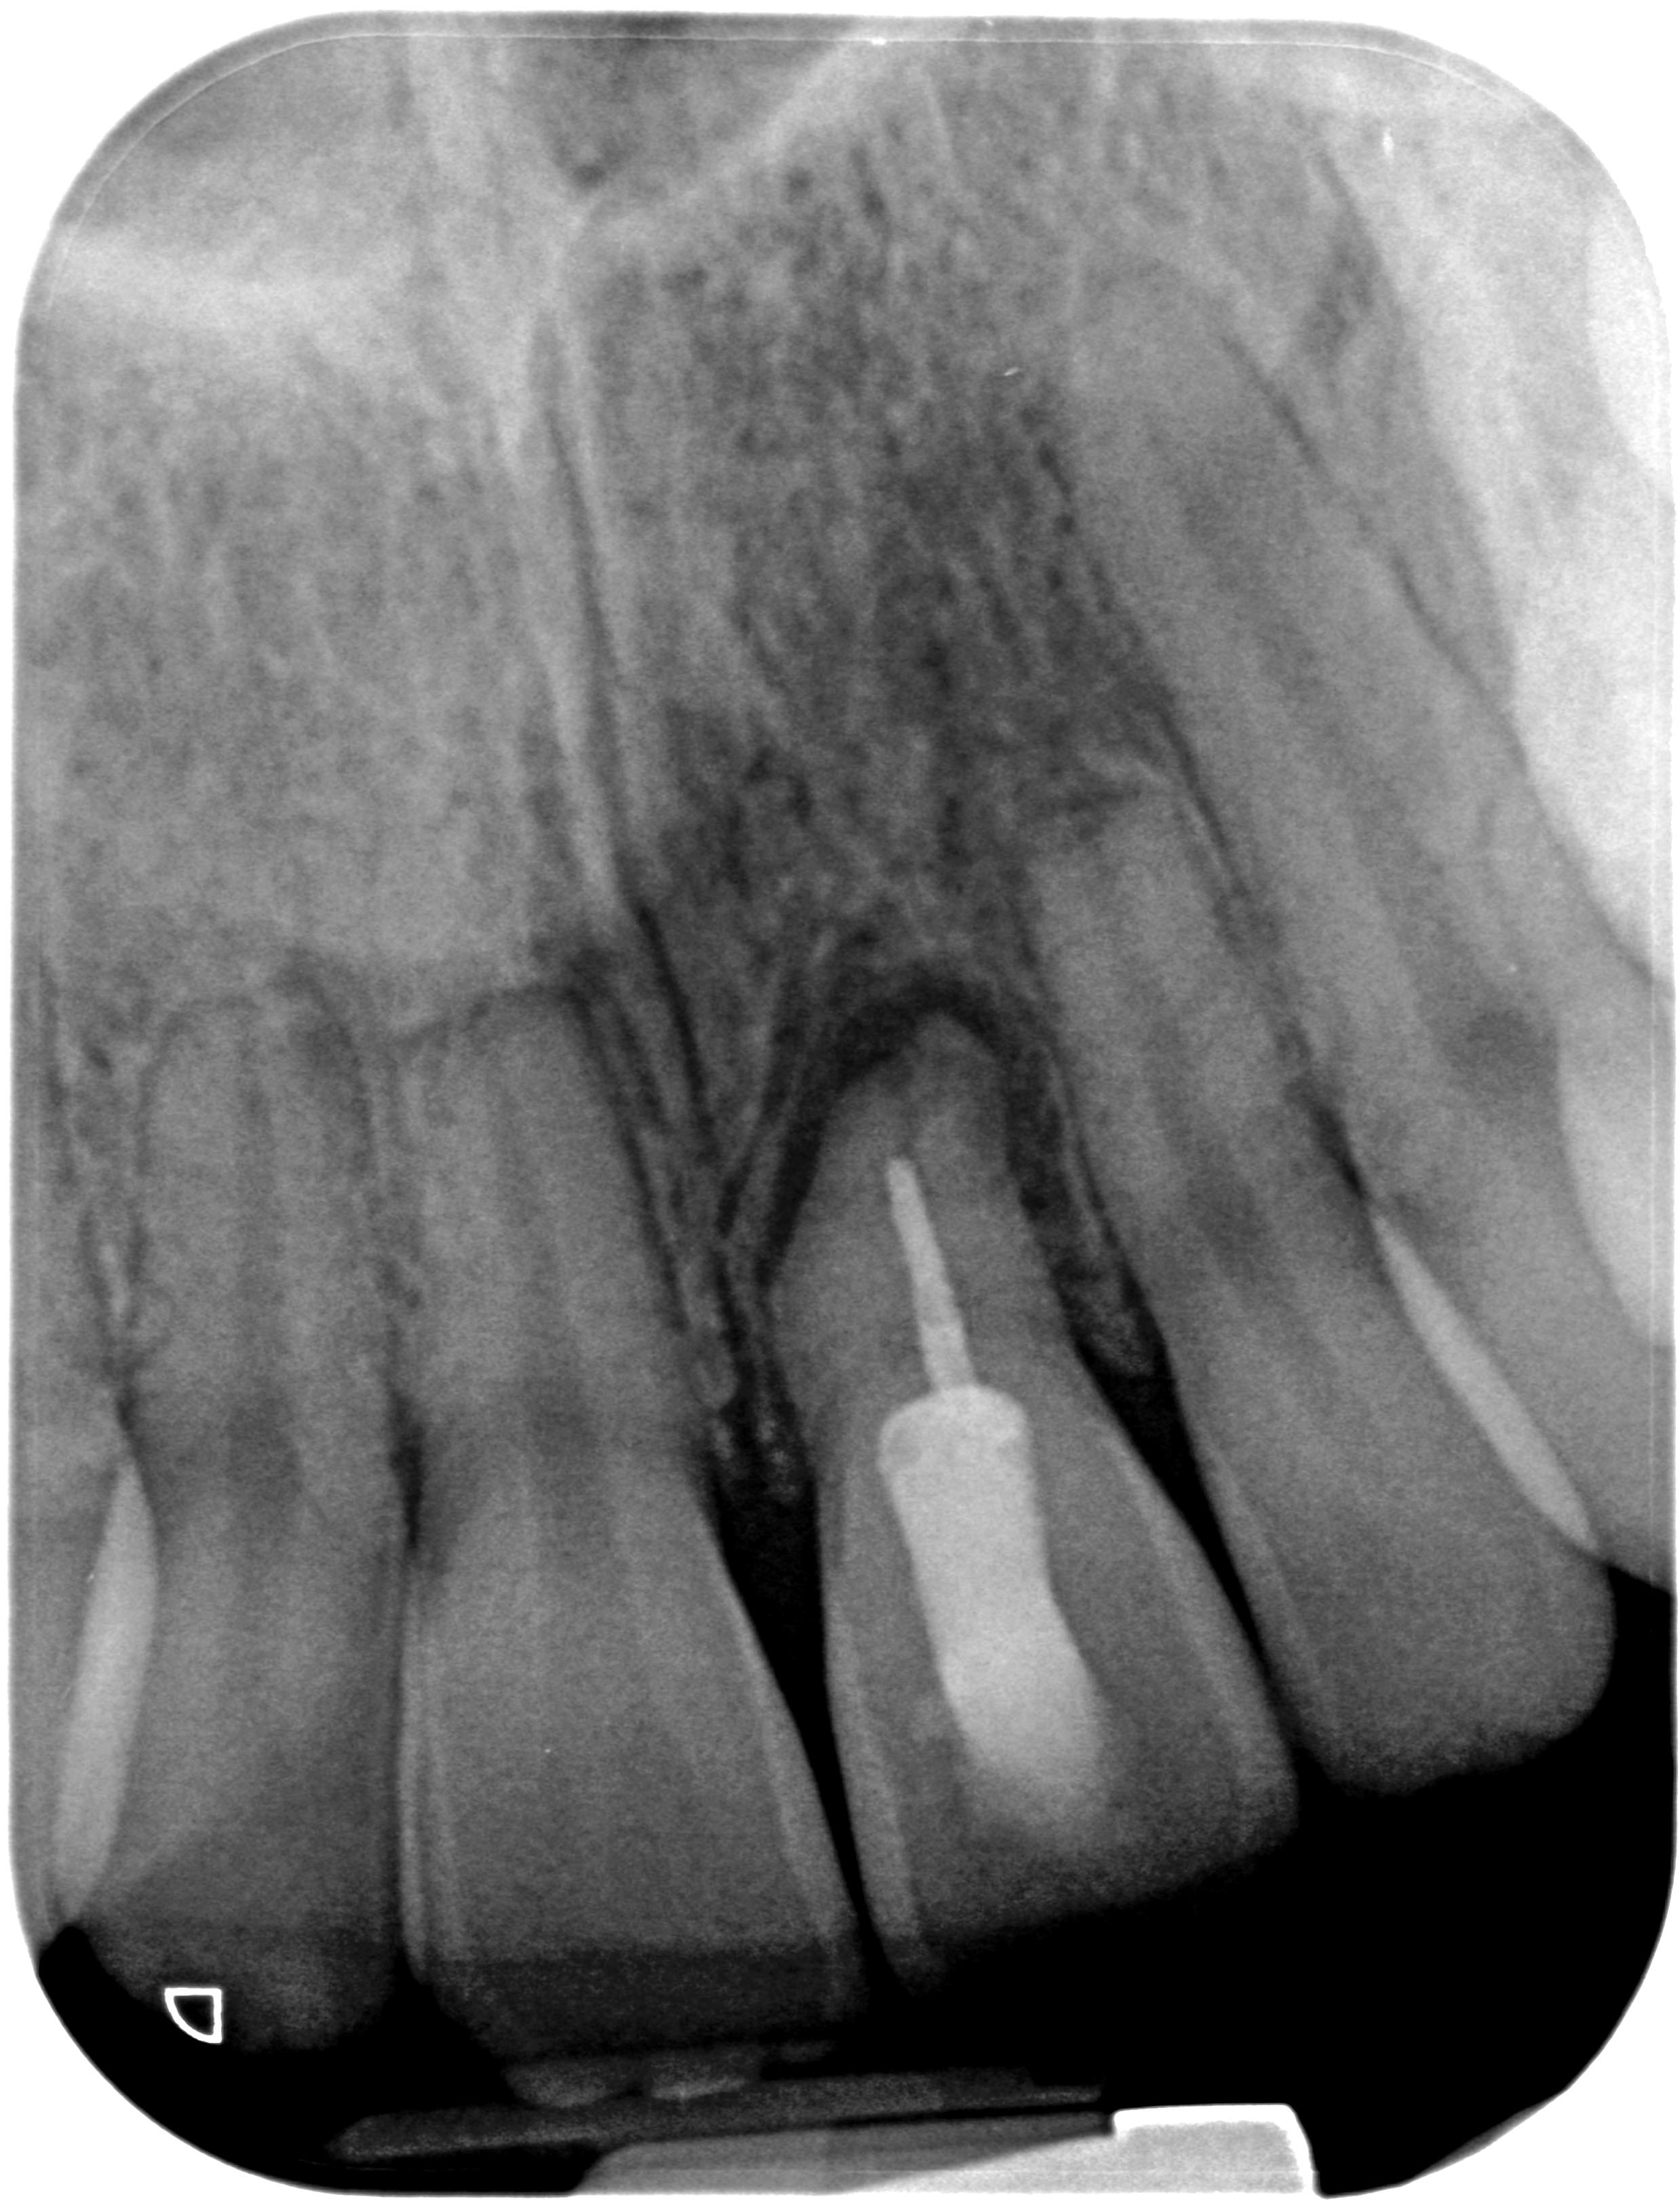

SL21_RD-1 Veröffentlicht 16. Dezember 2013 am 2476 × 3246 in Hoffnungsloser Frontzahn – Lockerungsgrad 3 – Die Fortsetzung